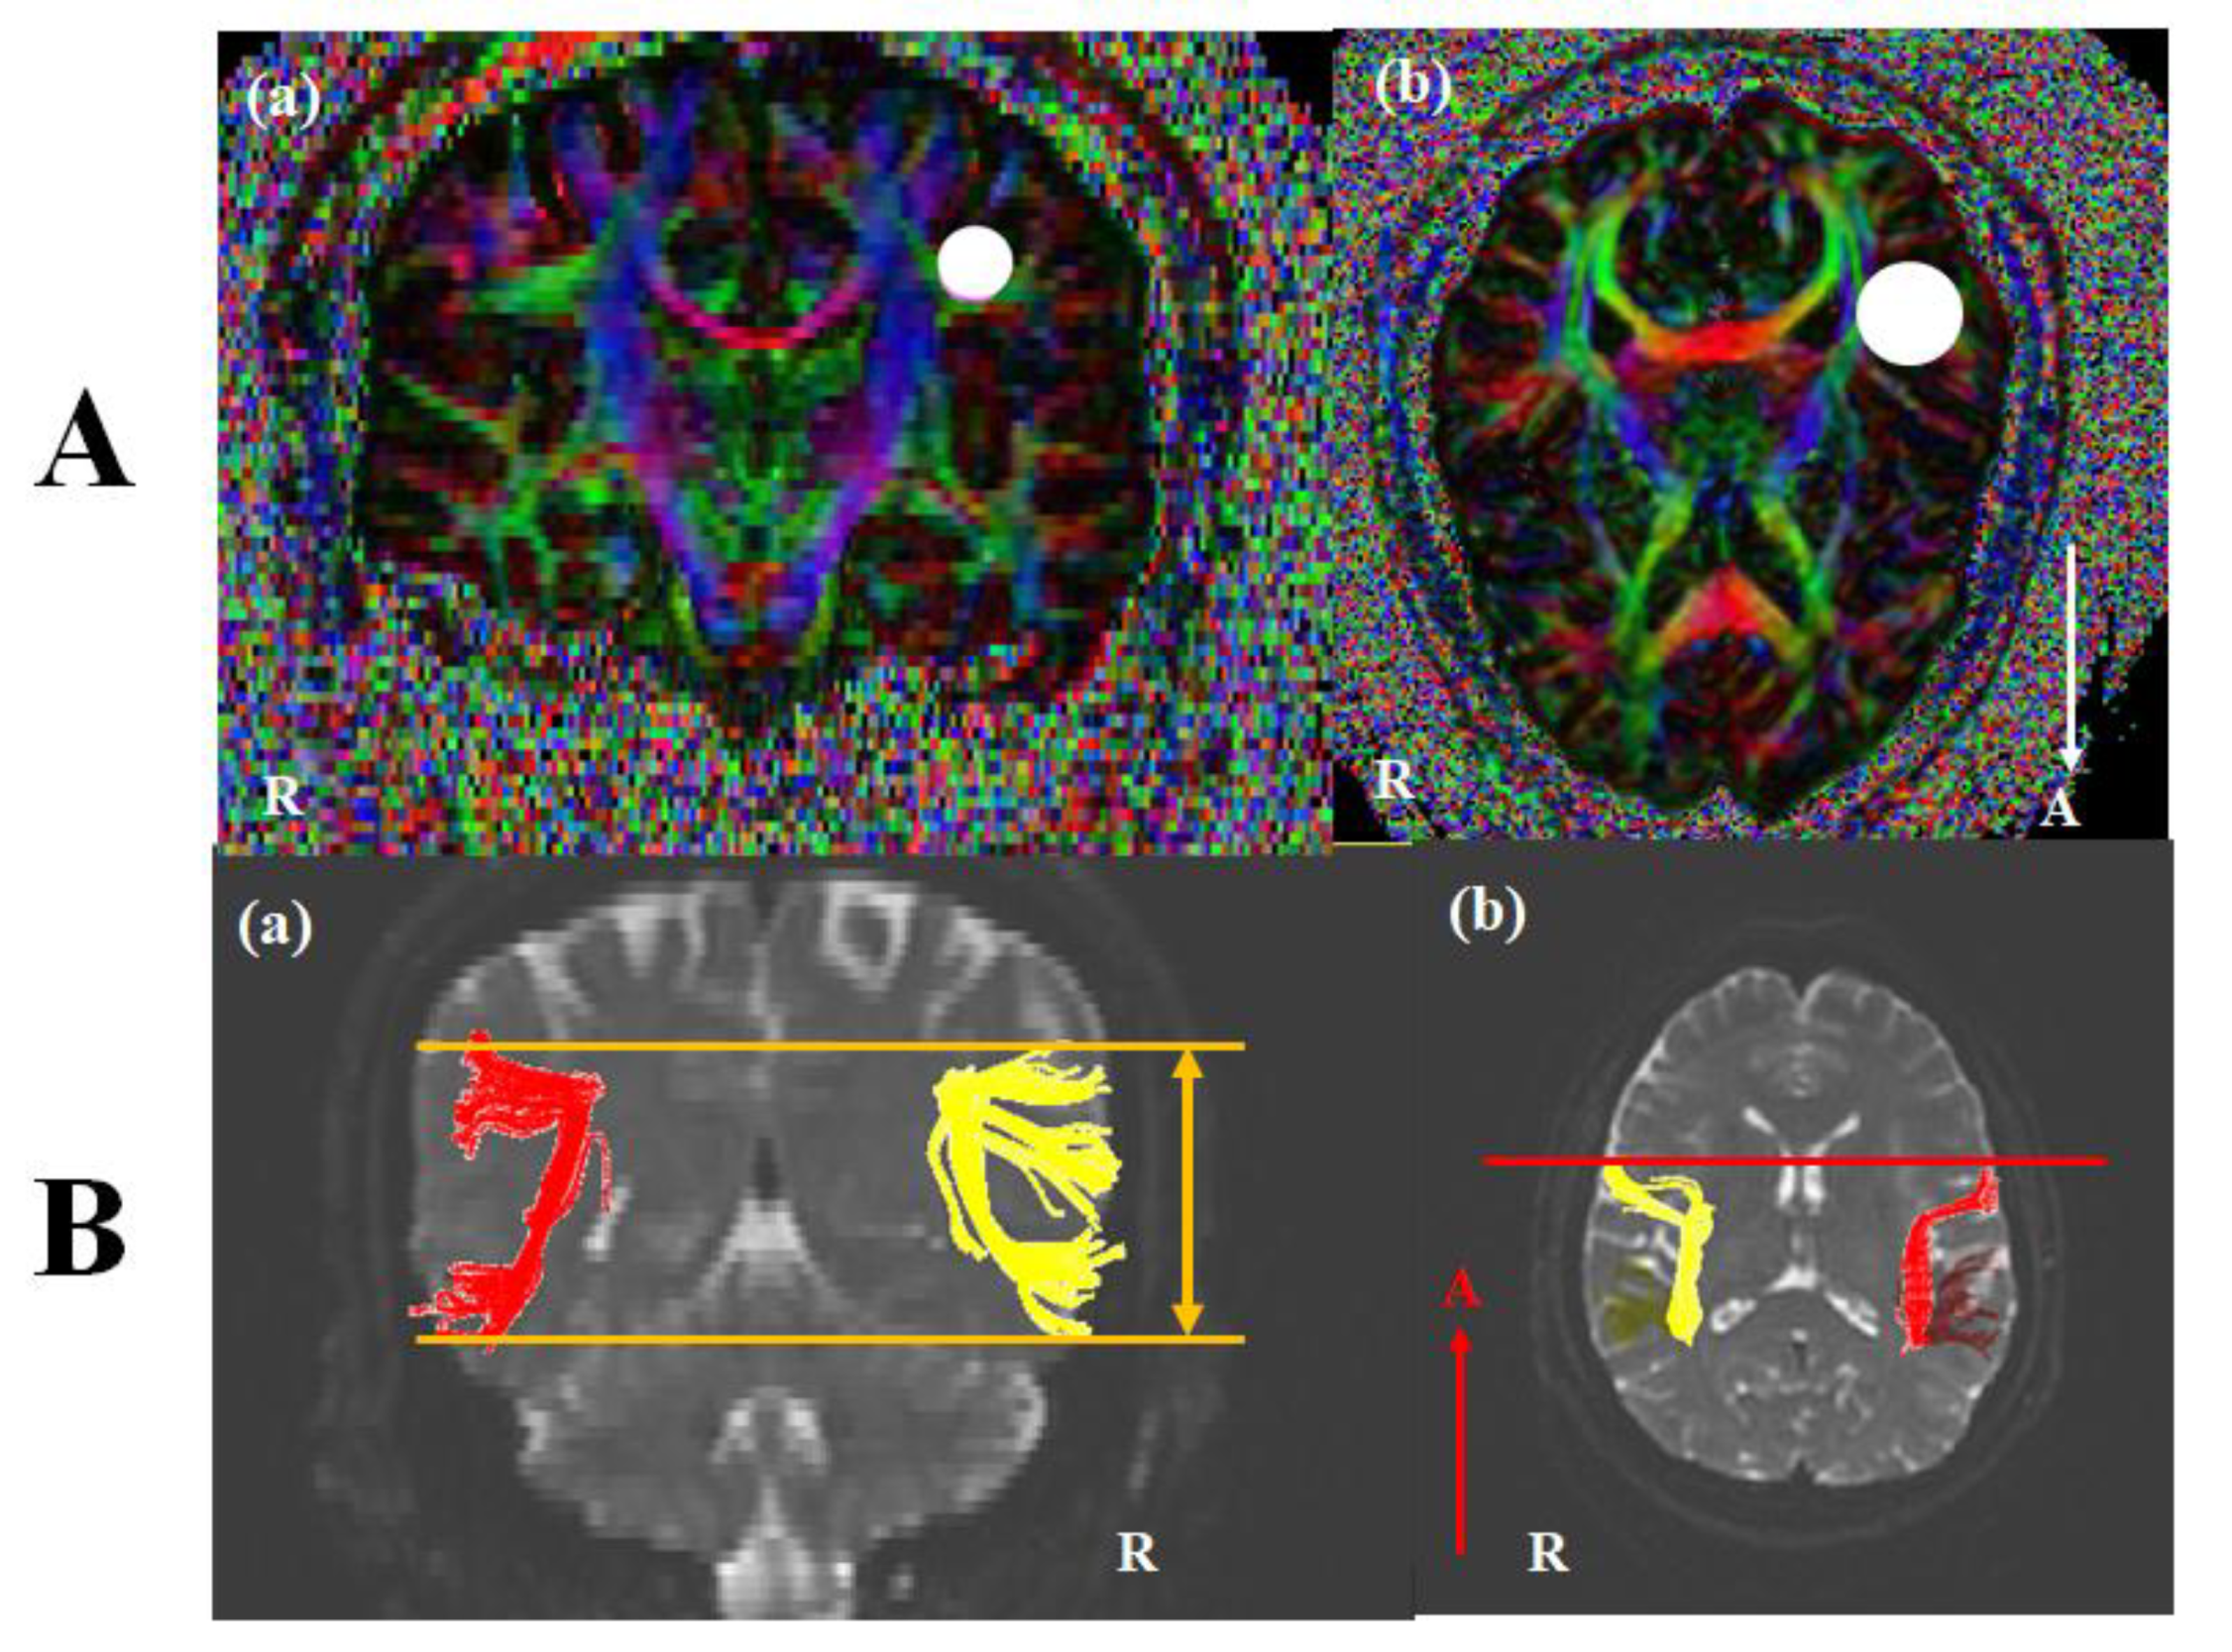

2. Materials and Methods

2.3. Diffusion Tensor Image